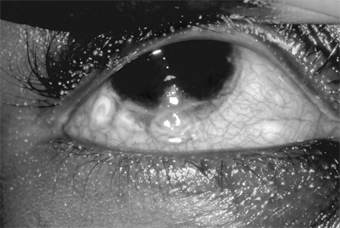

In adults, the conjunctiva of both tarsi-especially the lower tarsus-have papillae and follicles (Figure 5-3). Since pseudomembranes do not usually form in the adult, scarring does not usually occur. Superficial keratitis may be noted superiorly and, less often, a small superior micropannus (< 1-2 mm). Subepithelial opacities, usually marginal, often develop. Otitis media may occur as a result of infection of the auditory tube.

Figure 5-3

Figure 5-3: Acute follicular conjunctivitis caused by inclusion conjunctivitis in a 22-year-old man with urethritis. (Courtesy of K Tabbara.)